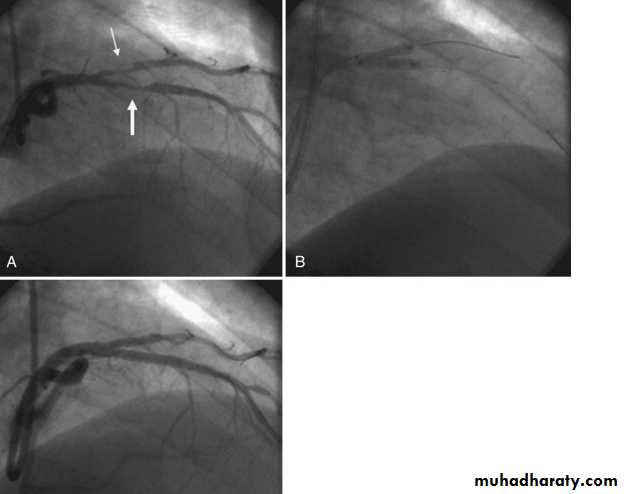

Severe proximal LAD Lesion

Very severe proximal LAD stenosis

Total CX Occlusion

Proximal LAD PCI

Bifurcational lesion PCI

Coronary Angiography

Gold standard to diagnose I.H.D. until nowDemonstrates the anatomy of the artery. By showing

1- severity of stenosis and type of the lesion

a- non-significant stenosis (<70%)

b- Mod or severe (Critical) lesion ( >70% )

2- Extent of the disease:-

single, two ,three vessel disease, Left main

stem disease (> 50%)